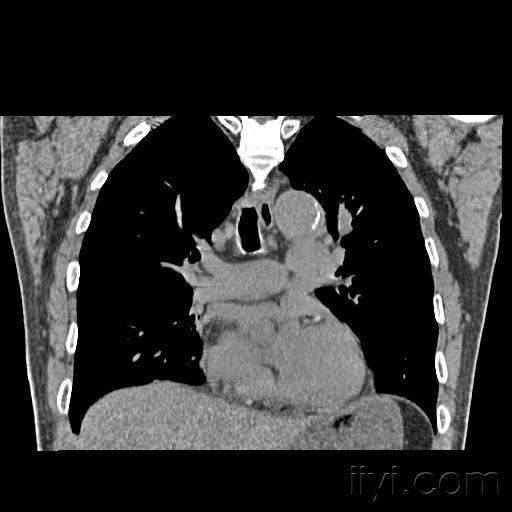

肺窗和纵隔窗

肺窗和纵隔窗,肺窗和纵膈窗

纵隔窗28.jpg

肺窗和纵隔窗区别

纵隔窗和肺窗的区别

肺窗和纵隔窗解剖图

纵隔窗

纵隔窗图片

ct纵隔窗图解